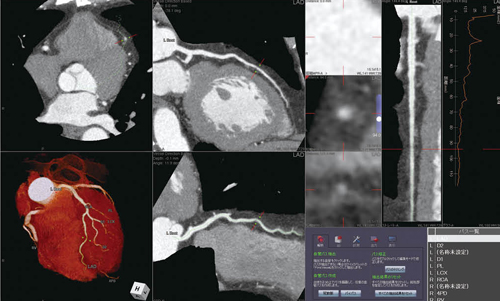

本田医長は、80列CTの高速撮影とあわせて、ziostation2のバージョンアップによって心臓の冠動脈解析などが可能になったことで、心臓CT検査の質と処理能力が大きく向上し、診断レベルが大きく変わったと語る。

「心臓カテーテルができない当院では、急性の心疾患が疑われる患者さんに対してCTによる冠動脈スリーニングを行って、ヘリによる緊急搬送か、経過観察かを判断しています。これまでも16列CTとziostation2を使って心臓CTを行っていましたが、主にCTの性能の部分で限界があり、息止め不可や頻脈などでCTの適応にならない場合や、撮影できても判断が難しい症例では、CTの再検査も含めて本土へ紹介せざるを得ませんでした。CTの高速化とziostation2の処理能力の向上で適応の壁がなくなり、より正確に確信を持って患者を振り分けられるようになりました」

同院では、急性の心疾患に対しては心臓CTを実施し、ziostation2のCT冠動脈解析2を用いて主要3枝の抽出、Angio Graphic ViewやCPR、MIPなどの解析を行い、搬送時には画像および解析結果を保存したCDを作成してデータを提供している。安田主任は、心臓CTの解析におけるziostation2の運用について、「処理能力の向上はもちろんですが、ネットワーク型になったことで至適フェーズを特定してから、冠動脈の解析作業を手分けして行えるようになり、処理時間が大きく短縮しました。また、冠動脈解析についてもバージョンアップによって中心線の抽出精度が向上しており、精度の向上と時間の短縮に繋がっています」と評価する。実際にバージョンアップ以後、心臓CTの検査数が増加し、導入後の2か月間で前年と同数の検査を実施したとのことだ。

CT冠動脈解析による冠動脈スクリーニング